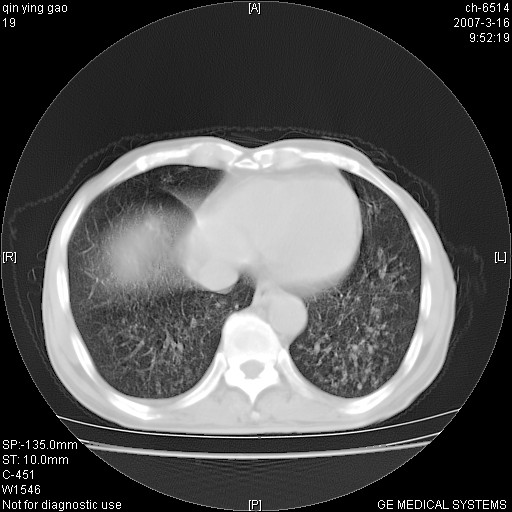

两中上肺见有广泛新老不一的结节灶,并伴有纤维索条影,血沉加快,白细胞不高,首先考虑结核。

双肺可见大小不等结节状密度增高影,密度不均,分布不均(双肺上叶为著),亚急性血行播散性肺结核.

(本例特征:以大小不等结节为主,主要分布在双上肺,并部分病灶融合成较大结节,期间搀杂诸多细小结节。从病灶特点与分布形式分析,更趋向于感染。)

两中上肺见有广泛分布大小不一的结节灶及斑片状影,部分融合,双下肺未见异常密度影,纵隔无明显肿大淋巴结,血沉加快,白细胞不高,首先考虑结核。 建议结合ppd检查或痰培养排除其他非特异性炎症。

中上肺野密布棉团状影,以胸膜下区为界,边缘模糊,可能是小叶或腺泡渗出及实变。全肺野弥漫分布网线样影及细小粟粒样影,可能是细支气管炎及间质内炎症。综合分析应首先考虑气道播散性感染,而肺内多处斑点性钙化,强烈提示陈旧结核复发并支气管播散。建议详细讯问病史